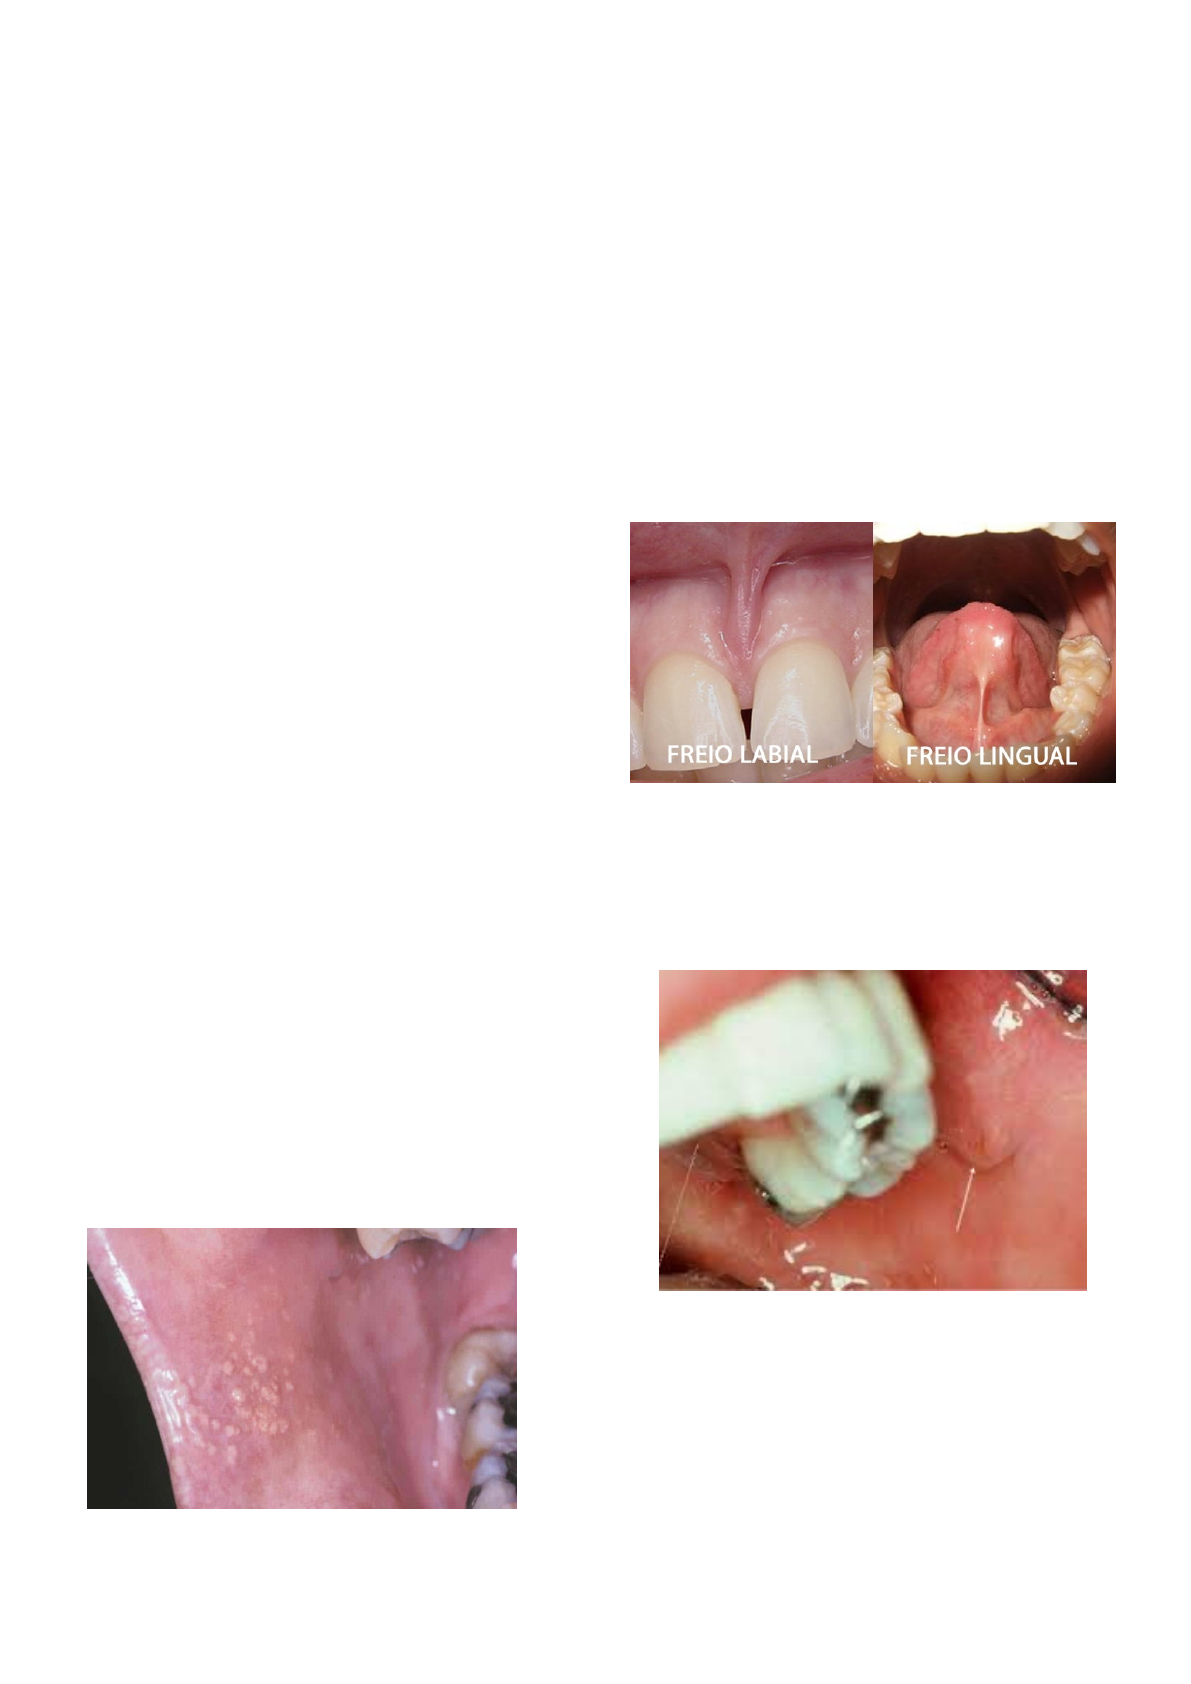

FRÊNULOS E FREIOS LABIAIS E LINGUAIS

Normalmente a inserção do freio se dá na

região de gengiva inserida e mucosa labial

Alguns pacientes tem a inserção do freio mais

baixo => causando diastema

Anquiologlossia: língua presa => isquemia do

freio